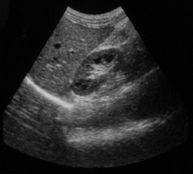

高清晰图像: